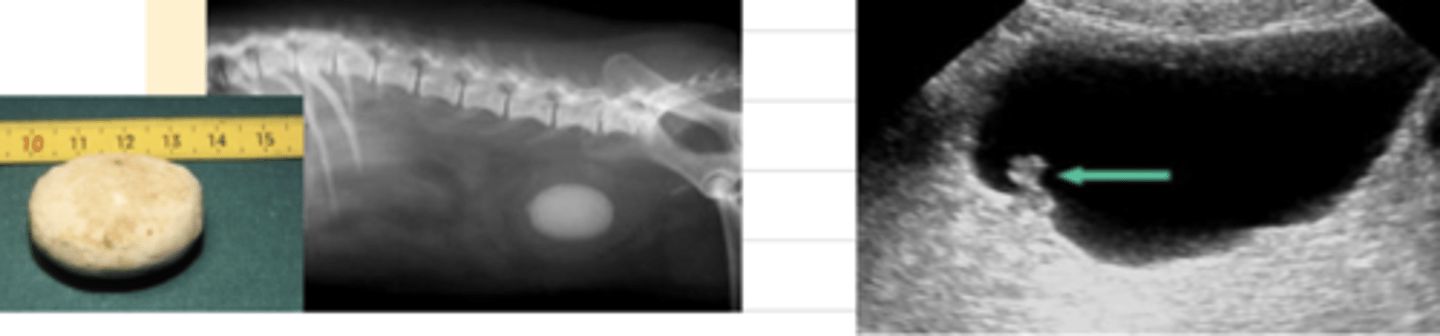

how can we diagnose uroliths?

easiest way is with imaging: xrays and ultrasounds